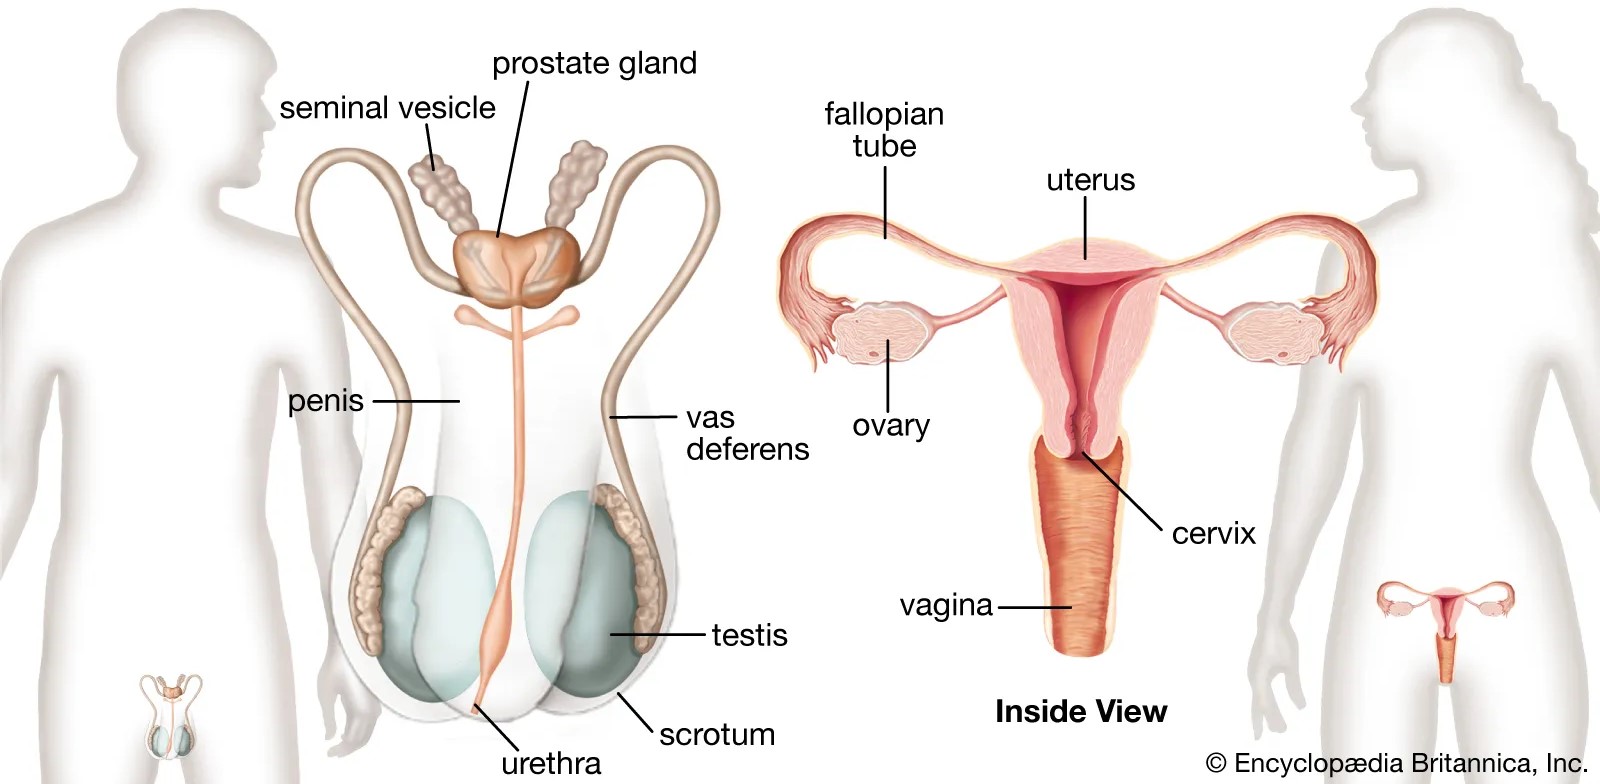

reproductive tract